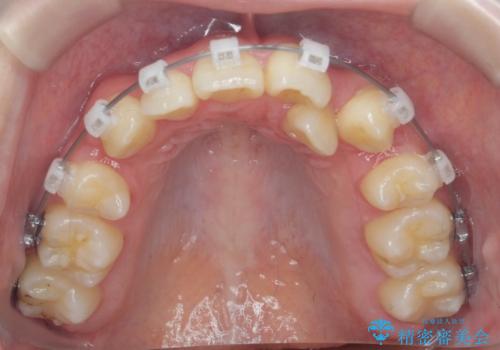

歯並びのせいで歯ブラシがしづらい マルチブラケットを用いた抜歯矯正

- 歯並びのがたつきにより歯ブラシがしづらく、今後虫歯になってしまう不安から、矯正治療を希望されて来院されました。

歯を並べるにはスペースが不足しているため、小臼歯の抜歯を4本行うマルチブラケット矯正による治療を計画します。